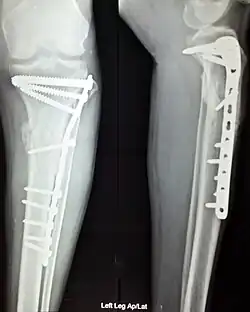

Orthopedic surgery or orthopedics (alternative spelling orthopaedics) is the branch of surgery concerned with conditions involving the musculoskeletal system.[1] Orthopedic surgeons use both surgical and nonsurgical means to treat musculoskeletal trauma, spine diseases, sports injuries, degenerative diseases, infections, tumors and congenital disorders.

The use of intramedullary rods to treat fractures of the femur and tibia was pioneered by Gerhard Küntscher of Germany. This made a noticeable difference to the speed of recovery of injured German soldiers during World War II and led to more widespread adoption of intramedullary fixation of fractures in the rest of the world. Traction was the standard method of treating thigh bone fractures until the late 1970s, though, when the Harborview Medical Center group in Seattle popularized intramedullary fixation without opening up the fracture.

- Repair of ankle fracture (bimalleolar type)

- Repair of ankle fracture (fibula)